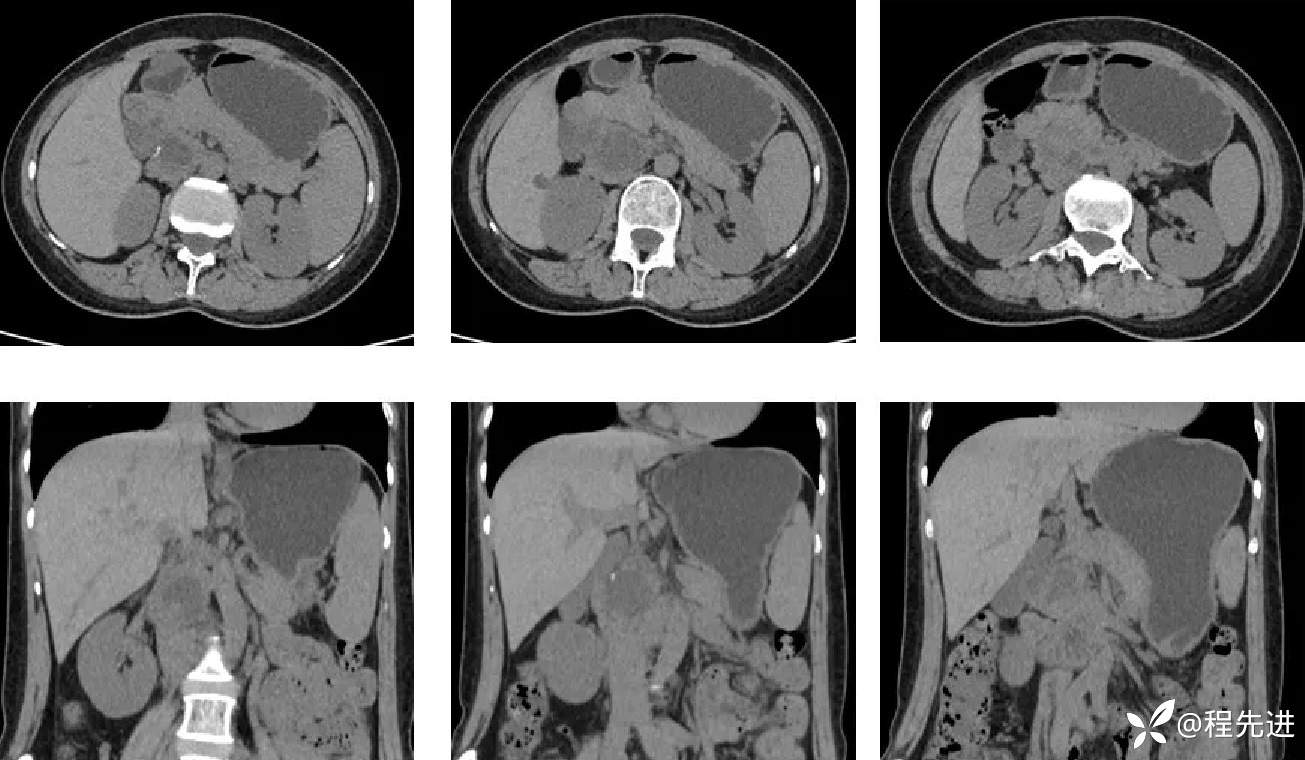

CT平扫: